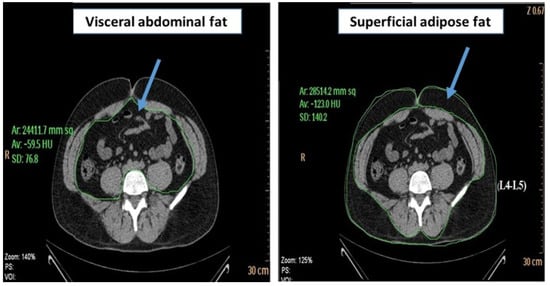

2.6. Assessment of Visceral Fat

The content of abdominal adipose tissue was measured with CT scans at the L4–L5 vertebra level. Subjects were in the supine position with both arms stretched above their heads. A single 6 mm slice was taken during respiration after a normal expiration. The total abdominal adipose tissue (TAT) area was measured and computed using an attenuation range of −190 to −30 HU. The quantification of visceral abdominal fat (VAT) was performed by delineating the abdominal cavity at the abdominal wall’s internal aspect and the vertebral body’s posterior aspect. Superficial adipose fat (SAT) was calculated as VAT area minus TAT area (Figure 4). VAT and SAT volumes were obtained by multiplying the area for each fat component by the slice thickness [25].

Figure 4.

Computed-tomography section showing visceral abdominal fat and superficial adipose fat.